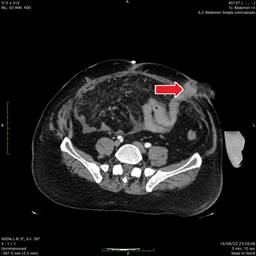

Paciente masculino de 48 años con antecedentes de poliomielitis sin secuelas aparentes durante la edad adulta. Inicia su padecimiento con abdomen agudo de causa probable apendicitis diagnosticado y atendido en hospital particular, se realiza laparoscopia con conversión a cirugía abierta, durante la cirugía se observa tumoración de yeyuno proximal (a 30 cm de ángulo de Treitz) (Figura 1), se realiza resección de 40 cm de yeyuno con anastomosis laterolateral con grapadora lineal, presentando fuga por dehiscencia de anastomosis a las 24 horas, por lo que se le realiza yeyunostomía a nivel de anastomosis, paciente con desarrollo tórpido y datos de sepsis abdominal, por lo que se envía a nuestra unidad por falta de recursos económicos.

Figura 1: Tomografía computarizada en corte axial en donde se observa la cuarta porción duodenal cercano al ángulo de Treitz y 30 cm restantes con salida a estoma yeyunal. Se encuentra dehiscencia en la aponeurosis de los músculos rectos abdominales.